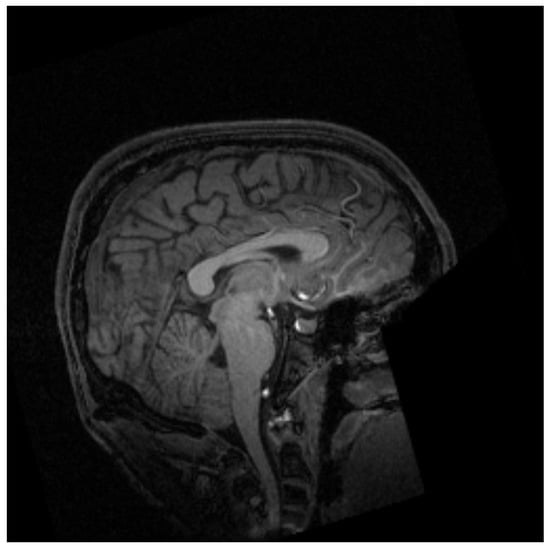

MRI is a non-invasive technique widely used in medicine to obtain the necessary medical images for further diagnosis. This technique is based on the physical phenomenon of resonance. It consists of the transition between different energy states when an atomic nucleus is introduced into an external magnetic field of a characteristic frequency. This frequency, known as the Larmor frequency, corresponds to the precession frequency of the protons inside the nucleus. When a magnetic field is applied, the protons absorb the energy and raise it to a higher level. Once the magnetic field is removed, the protons decay to the ground state. MRI measures the time and energy released from this last transition. Due to its environment, those two values will be different for each proton. Then, applying the inverse Fourier transform to the obtained data, the image is created with different contrast for each component of the body [14] as shown in Figure 1.

Figure 1. Example of magnetic resonance imaging of the cranial region [15].

Figure 4. Images of sagittal, coronal and 3D slices of the brain. The blue line shows the plane corresponding to the image in Figure 3.